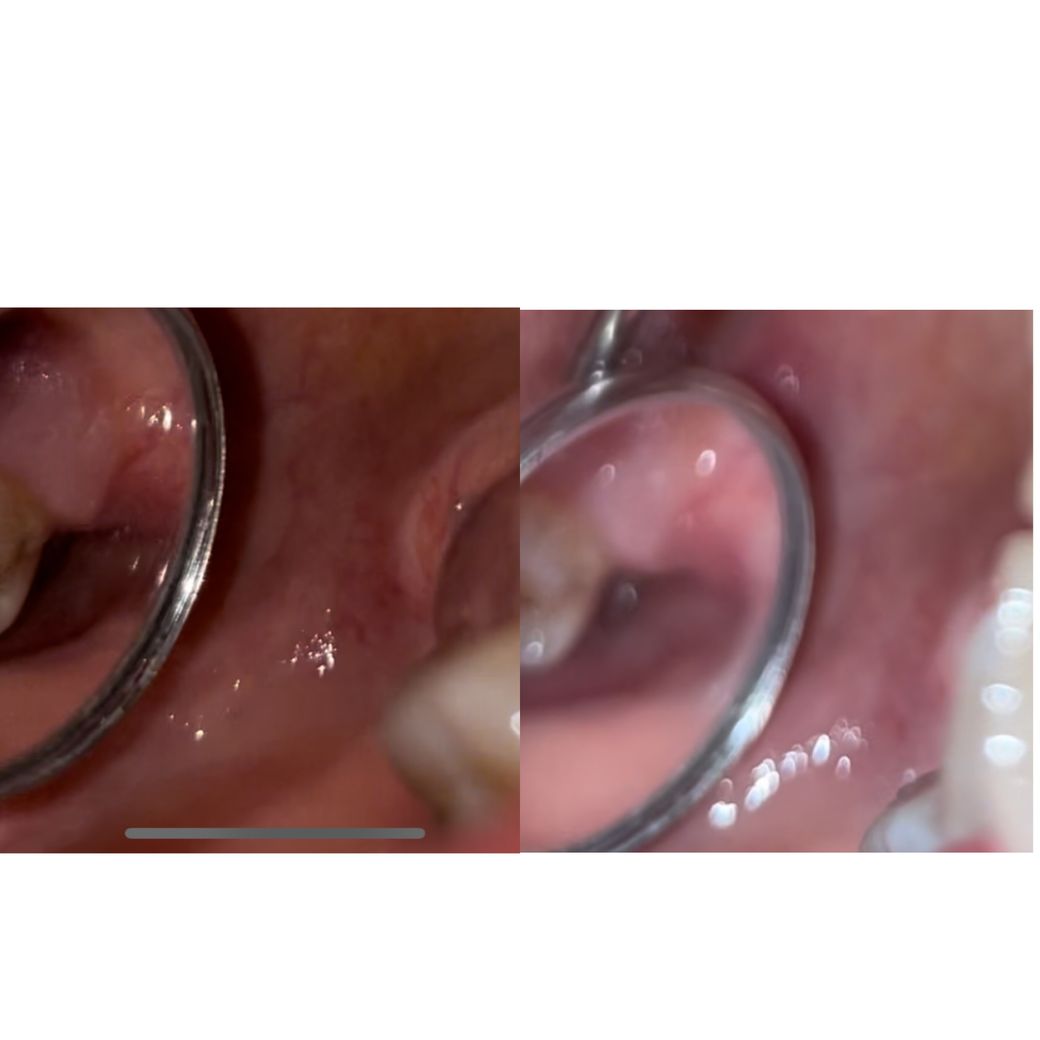

헐레벌떡 어제 (10.13)치경으로 막 보는데

뭐가 차있는 느낌은 없고 빵꾸 뚫려있는거같은데..내부에 피딱지가 있는건가요?? 그래서 제 눈에 안보이는건지..

사진은 10.13일 밤 기준입니다!

정상적인 회복 과정입니다. 혈병이라는 것이 초기에는 눈에 잘 보이나 1~2일이 지나면 일반인들은 구분하기가 쉽지 않습니다. 현재 주변 잇몸 색이나 회복되는 것을 보았을 때 정상적으로 보여지며 약간의 통증 및 불편감은 보통 잇몸이 모두 상피로 덮힐때까지는 조금씩 있을 수 밖에 없습니다. 드라이소켓이라면 약간의 통증이 아닌 극심한 통증으로 보통 견디지 못할 정도로 나타납니다. 따라서 정상적인 회복 과정이니 걱정하지 마시길 바랍니다.